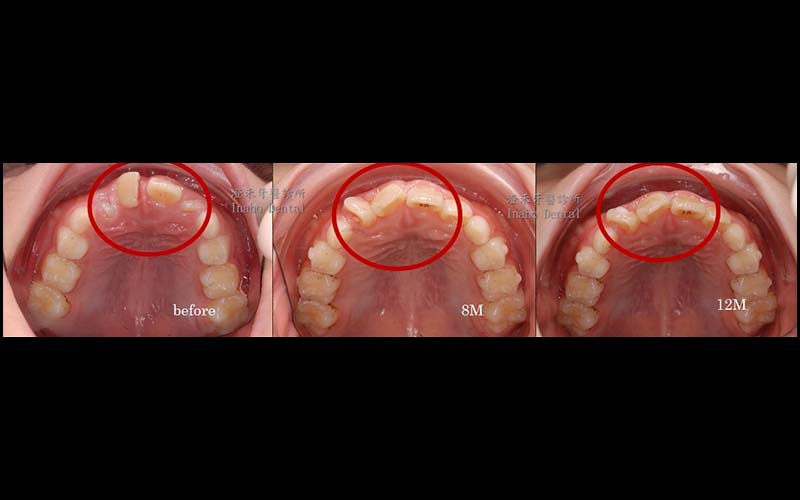

年齡:8歲

媽媽希望提早改善他牙齒凌亂不整齊,因門牙不易咀嚼食物,配戴了隱適美矯正器後,漸漸讓牙齒變整齊了,食慾也變好了。在黃金時期改善咬合不正,讓學童在生長發育的過程中可以更順利。

目前已矯正12個月